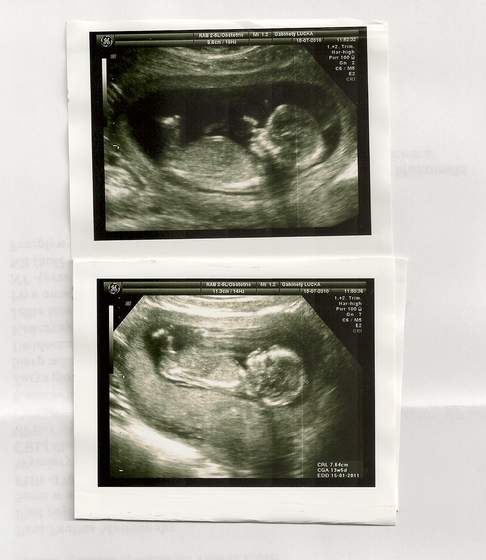

A ja dzisiaj byłam na usg. Okazało sie, ze maluszek jest o tydzien starszy niz na suwaczku, 13t5d, ma 7,7 cm wzrostu

Takze jestem dumna z mojego dzidziusia. Wszystko jest w porzadku wrecz ksiazkowo. Dostalismy kilka zdjec i płyte CD. Oczywiscie byl ze mna narzeczony. A co najlepsze znamy płeć

a oto ON: